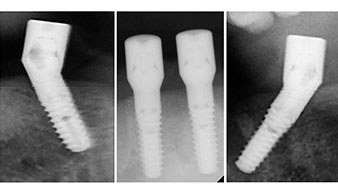

A three-dimensional cone beam computed tomography scan (CBCT, Planmeca) was performed to aid planning and minimize risks. This revealed that the quality and quantity of the available bone were sufficient for the surgery and immediate restoration using the Fast & Fixed method. Following the protocol for this concept, the implants are inserted at 35, 32, 42 and 45. Angling the distal implants by up to 45° shifts the emergence profile to posterior and generates a larger support polygon (Fig. 3).

This corresponds to the next preset position in the Implantmed. Here we see the W&H contra-angle handpiece being held at a 45° angle to mesiocaudal in the region of 45 in order to preserve the mental nerve. The mental foramen is used as the anatomic reference for all drilling in this region. The subsequent holes were drilled at a reduced speed of 300 rpm (Fig. 10 and 11).